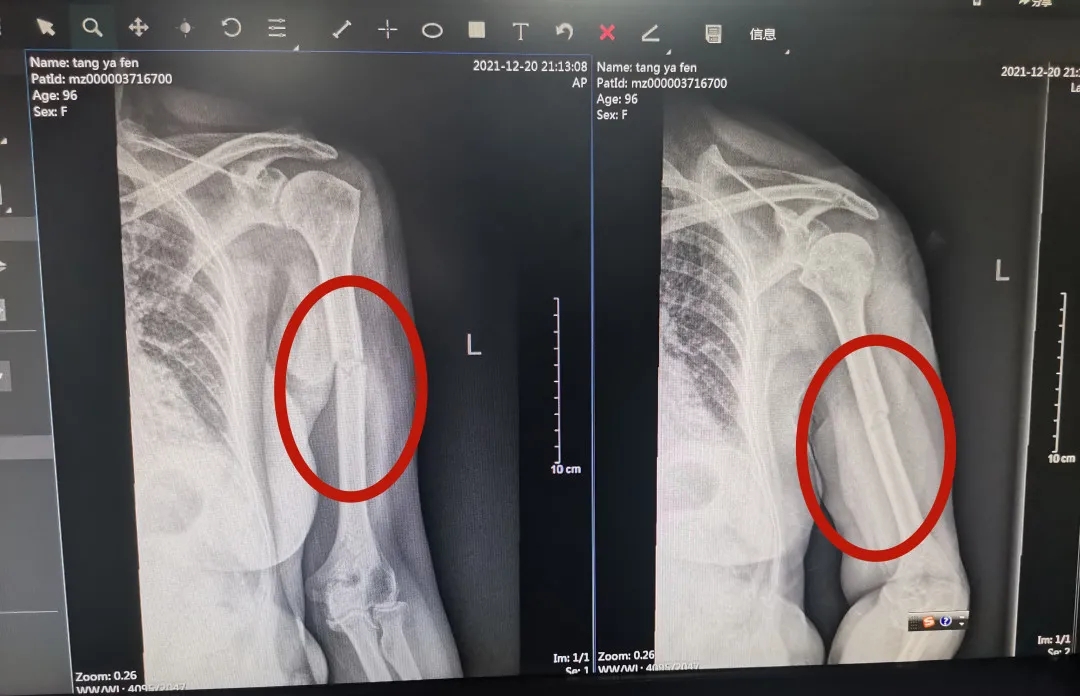

唐奶奶本次手术前X线检查结果

唐奶奶第二次手术后X线检查结果